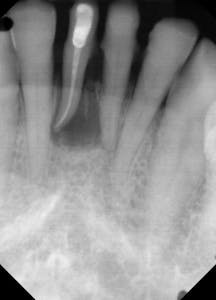

This is the case of a patient who has been missing a lower incisor for more than a year due to a failed root canal treatment (RCT). While there’s plenty of space mesiodistally, bone sounding helped us determine that there was only 4 mm of bone in the buccolingual dimension. A mini-implant was placed without raising a flap, the impression was taken at the time of surgery, and the implant was restored three weeks later.

Figure 1: Radiograph of pilot drill